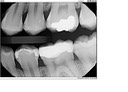

Scott Kanamori #12 pre-op